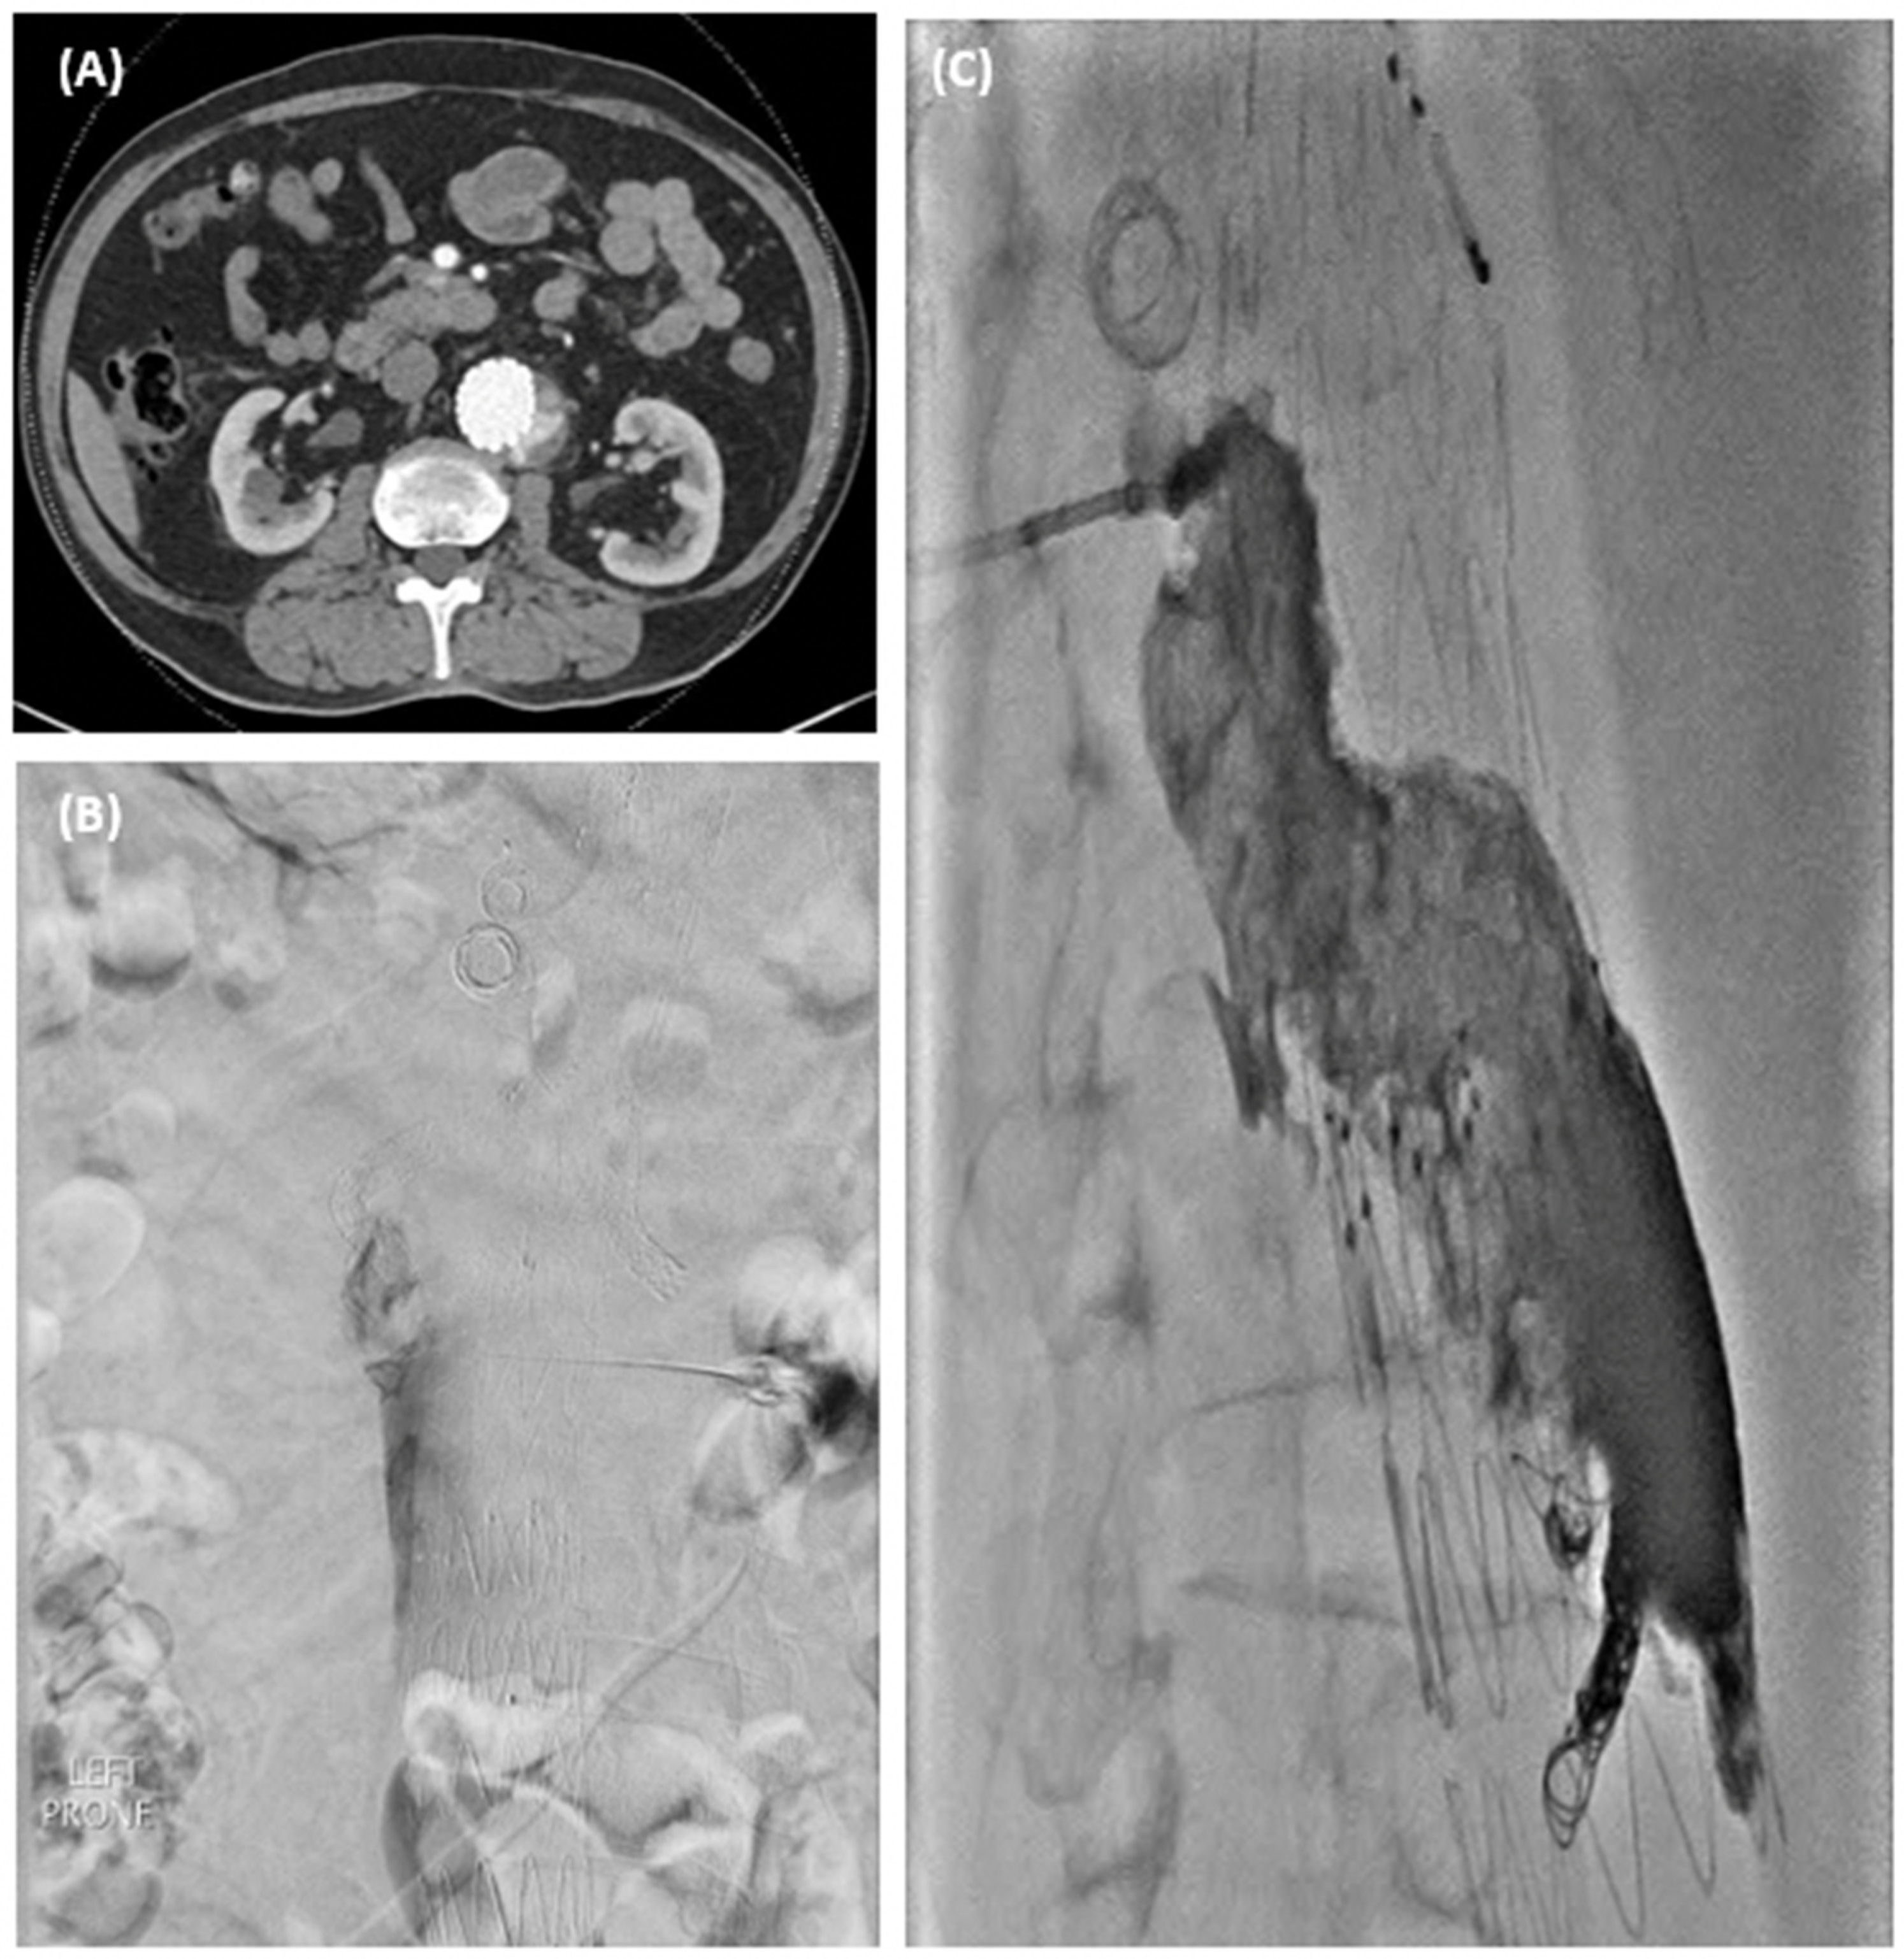

Branch occlusions | All > 1 year incidental on surveillance 4 renal—3 patients, 1 bilateral underwent thrombolysis, 2 unilateral—treated conservatively |

Aortic limb occlusion | 2 iliac limbs, required thrombolysis and relining |